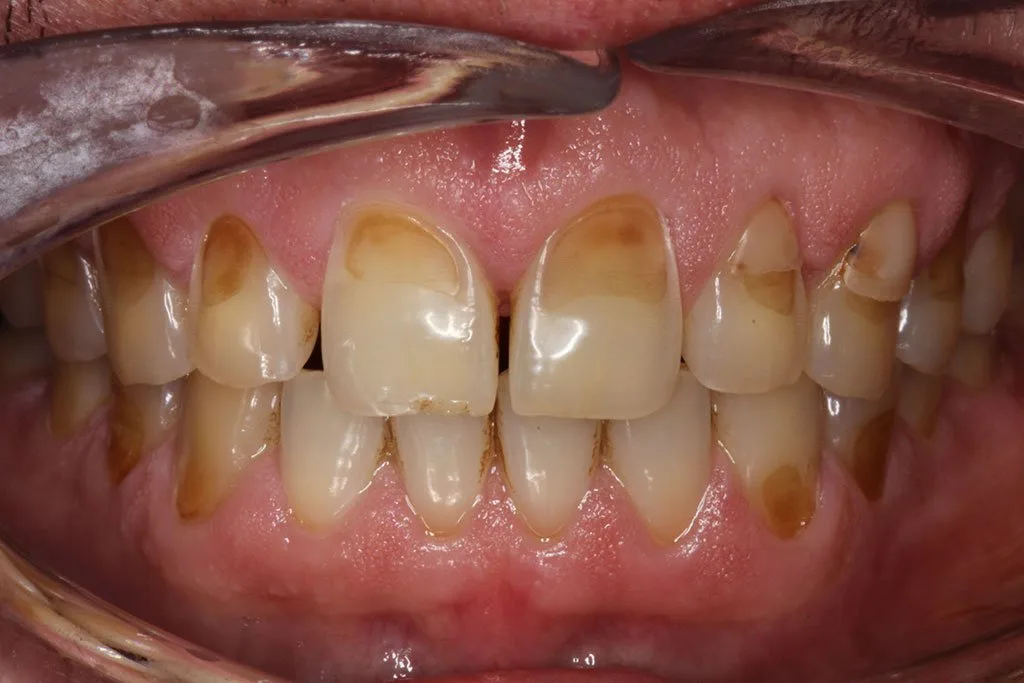

Hoy en día, el número de pacientes con un daño significativo en el esmalte de los dientes se ha incrementado. Entre los principales culpables se encuentran las bebidas gaseosas, bebidas energéticas, zumos de frutas ácidas, fruta y cualquier tipo de alimento ácido, además de las drogas que también pueden causar una severa erosión del esmalte.

Existen personas que tienen el esmalte de la parte superior o el de los lados perforados, y en casos más extremos, se dan individuos con erosión en completamente todos los dientes.

El daño del ácido puede ser muy grave y no solo en la erosión y rotura del diente, sino también en problemas como la sensibilidad dental. La reparación se realiza generalmente utilizando resina composit o coronas y carillas en los casos más graves.